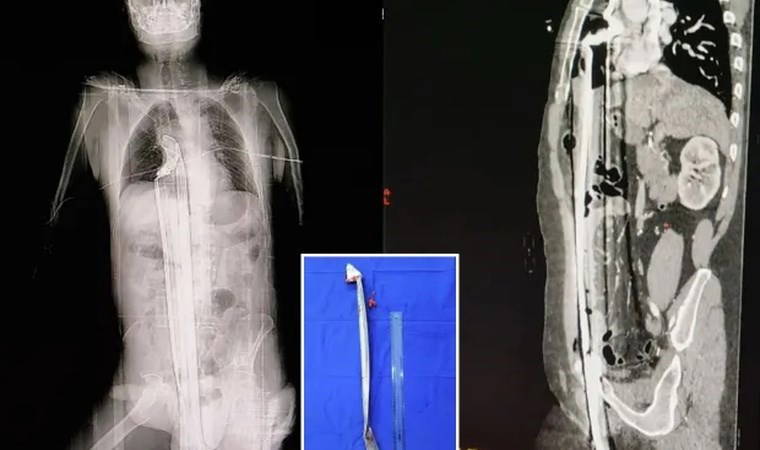

91 cm uzunluğunda demir çubuk çıkarıldı... 91 cm uzunluğunda demir çubuk çıkarıldı... Kayarak iskeleden düşen bir inşaat işçisi, perine bölgesine demir bir çubuğun saplanmasının ardından mucizevi bir şekilde ölümden kurtuldu.